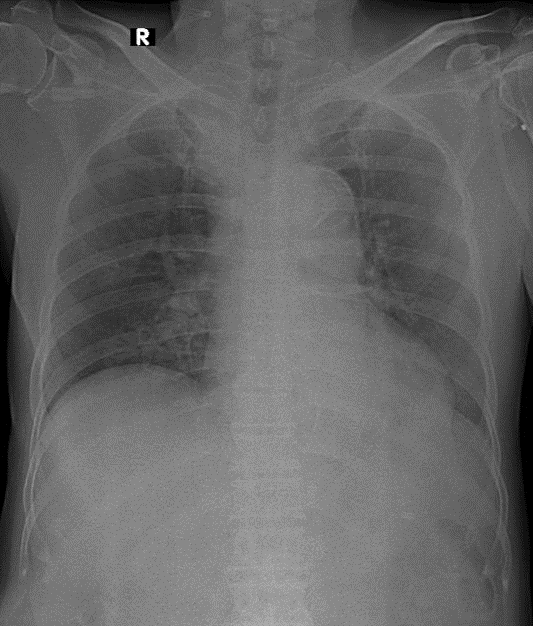

1-Thâm nhiễm phế nang lan tỏa thùy dưới phổi (P) 2-Cung động mạch chủ dãn 3-Cung động mạch chủ đóng vôi 4-Tim (T) lớn [dày thất trái ]